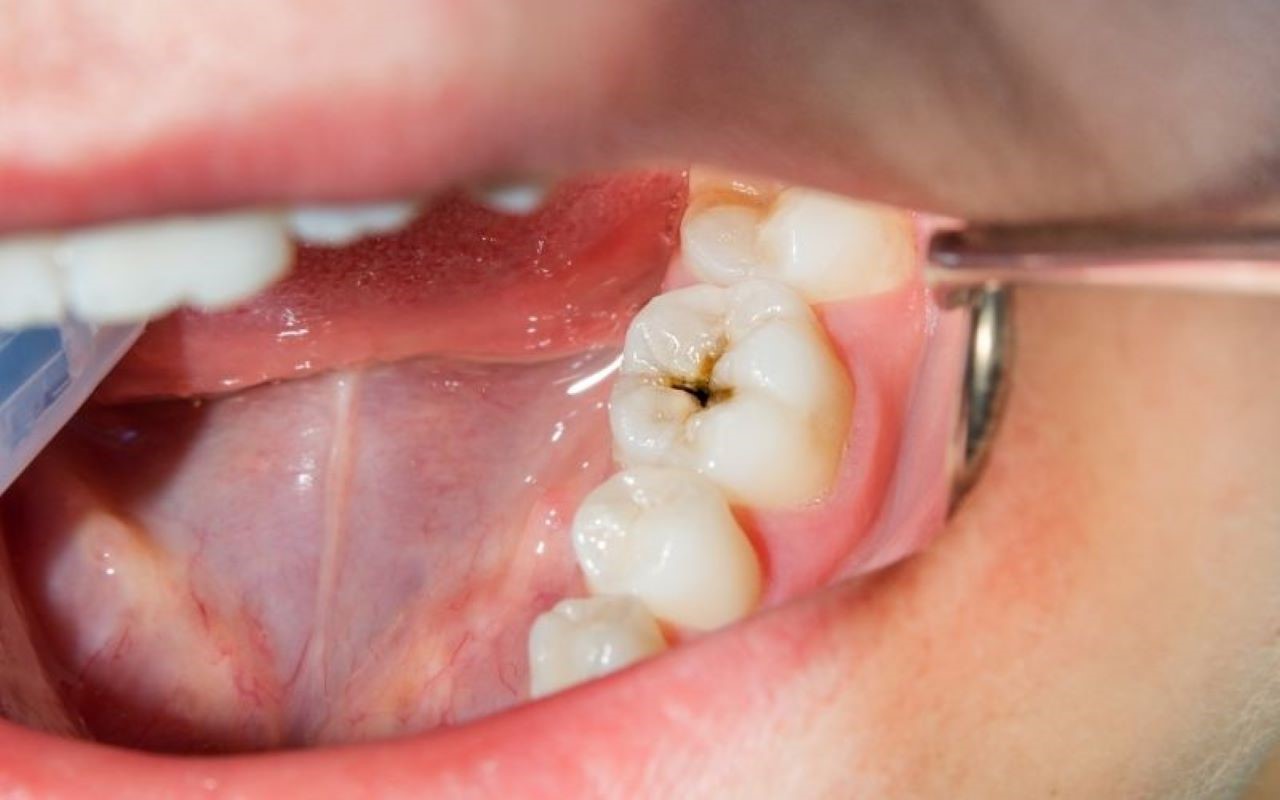

Sâu răng là nguyên nhân phổ biến dẫn đến viêm tủy. Khi lỗ sâu tiến sâu vào lớp ngà răng và không được trám lại, vi khuẩn sẽ dễ dàng tấn công vào tủy, gây viêm và hình thành ổ mủ.

(Sâu răng lâu ngày ở trẻ em hoặc người trưởng thành nếu không điều trị sẽ dẫn đến viêm tủy)(**)